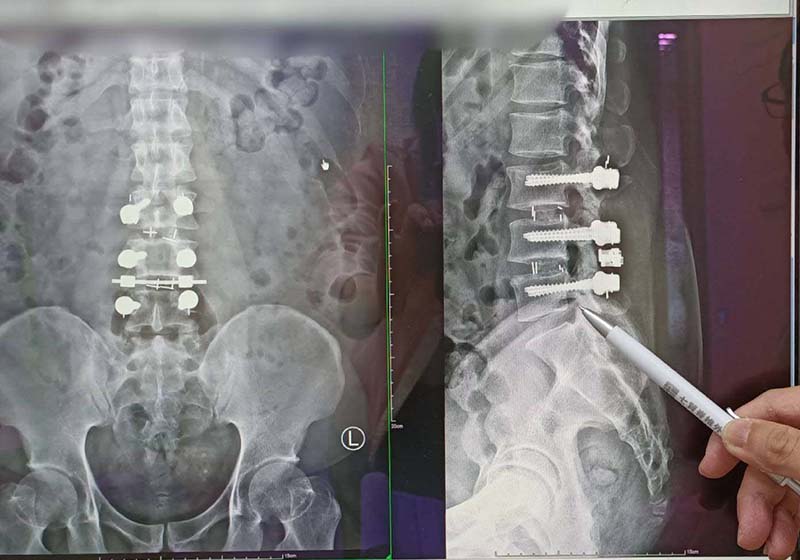

高市40歲朱姓男子民國99年在屏東從事工程業,35歲時常感腰痠背痛,甚至延伸腳踝,可謂坐立難安,手術未見改善,無法和友人打球及跑步,上網搜尋七賢脊椎外科醫院,經疼痛科副院長楊子旻確診腰薦椎椎間盤突出導致坐骨神經痛,建議施作高頻熱凝療法,術後隔天痛感消失,恢復正常生活,楊子旻說,高頻熱凝療法兼具疼痛感少、免住院、局部麻醉、未破壞神經阻斷痛覺等特性,透過電磁波加熱至42度,每秒刺激患部2次,每次20毫秒,適用坐骨神經、頸部、關節、五十肩、網球肘、背部、尾椎脊椎術後疼痛、足底筋膜炎等,治療後仍應維持理想體重、正確姿勢及避免搬重物,如有不適症狀速就醫檢查。圖/七賢脊椎外科醫院提供、文/高培德